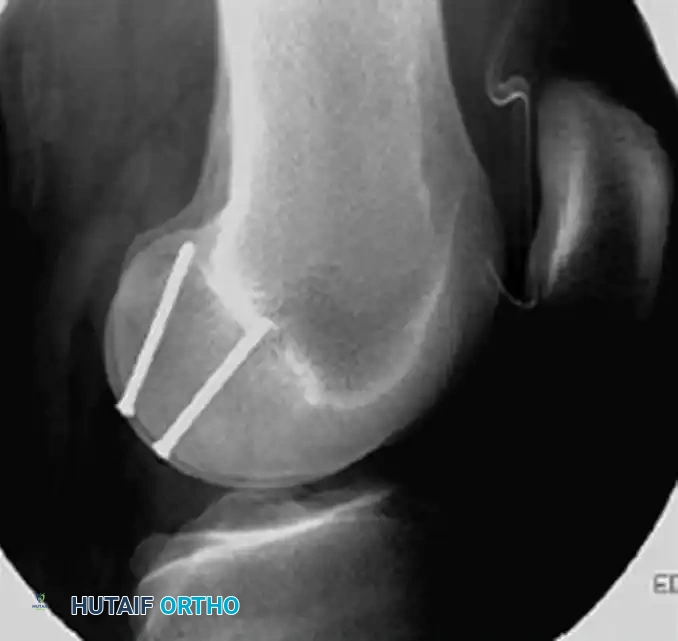

Lateral radiograph confirming the trajectory of the fixation screws, ensuring they do not breach the articular surface or the intercondylar notch.